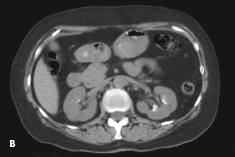

An abdominal radiograph (A) and a CT scan of the kidneys, ureters, and bladder (B) showed bilateral renal calcifications. On the right, the largest was 3 mm, and on the left, multiple punctate calcifications were evident. Urinalysis was positive for trace blood and trace leukocytes. The analysis of the stone revealed triamterene composition. The patient underwent successful placement of ureteral stents to help passage of the stones followed by lithotripsy.

Treatment consists of discontinuation of the medication and lithotripsy, because the calculi cannot be dissolved by pH manipulation.3 On plain radiographs, triamterene stones are—as in this case—faintly radio-paque and are less dense than calcium oxalate stones. They are more detectable on a CT scan of the kidneys, ureters, and bladder.